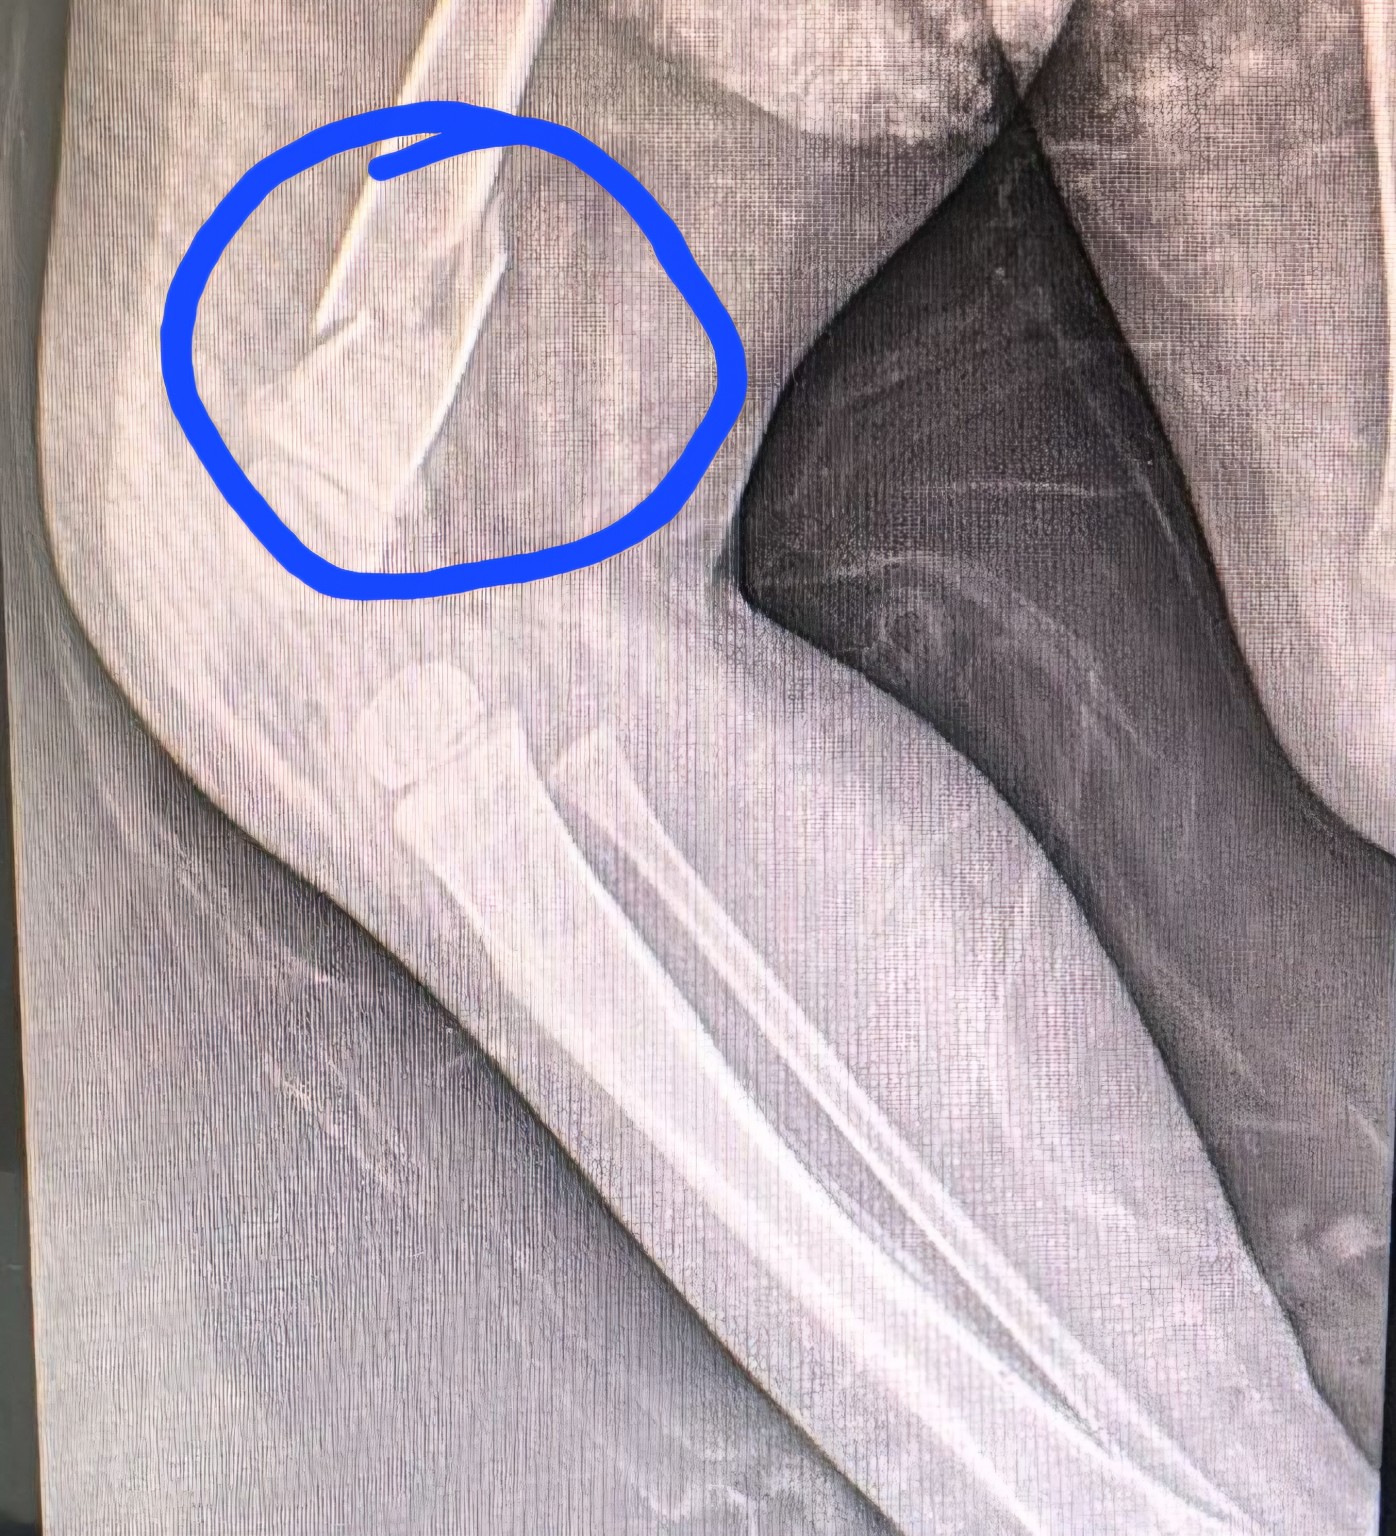

Um bebê de apenas 11 meses deu entrada na emergência do Hospital Santa Catarina, em Criciúma, com múltiplas lesões pelo corpo, incluindo uma fratura no fêmur, na noite desta sexta-feira (31). Diante da gravidade dos ferimentos, a equipe médica acionou a Polícia Militar.